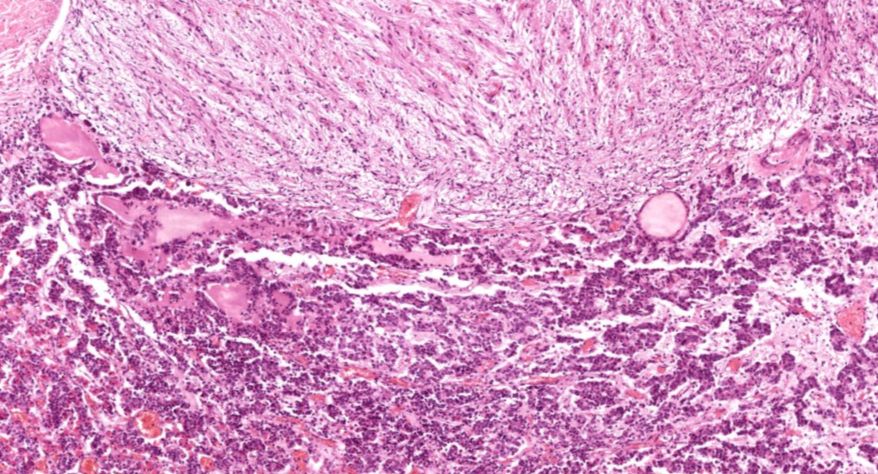

肾上腺

2.被膜

3.皮质